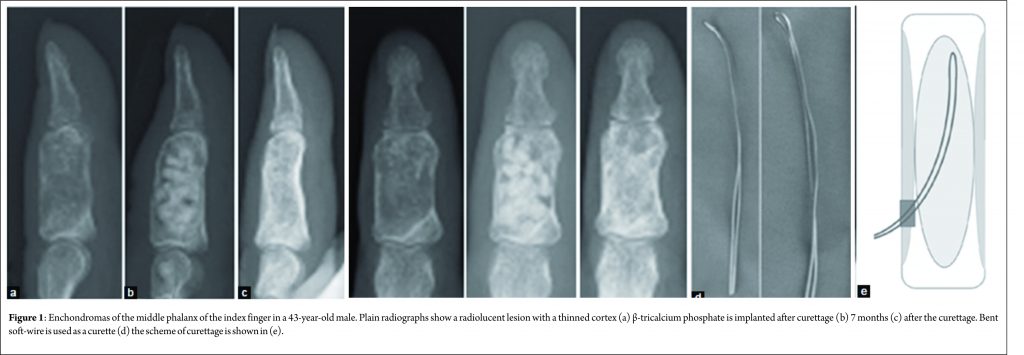

In the current article, two representative cases are presented. One is a 43-year-old male with enchondroma in the middle phalanx of the left index finger (Fig. 1), and the other is a 28-year-old female with enchondroma in the distal phalanx of the right thumb (Fig. 2). In both cases, the plain radiographs showed a radiolucent lesion with a thinned but expanded cortex. Both lesions have expanded to the whole bone. These features of the plain radiographs are typical of enchondroma. Surgery was performed in both cases under general anesthesia. The cortex adjacent to the lesion was approached dorsally, splitting the extensor tendon (the index finger case), or laterally (the thumb case). Fenestration of the cortex was performed with a 3.2-4 mm diameter surgical air drill. A bent and looped soft-wire of 0.7 or 0.9 mm diameter was threaded through the fenestration and used as a curette (Fig. 2). Complete access of the soft-wire within the whole lesion was assessed and confirmed with a fluoroscopic image during the operation. Residual fragmented enchondroma tissue was washed away by saline using a syringe with a plastic needle. Consequently, β-tricalcium phosphate (TCP) particles were implanted (Fig. 1 and 2). The diagnosis of enchondroma was confirmed on the resected lesion. There were no complications associated with the operation. The range of motion in the adjacent joint was not restricted.

Technique: Two representative cases are presented: one is a 43-year-old male with enchondroma in the middle phalanx of the left index finger, and the other is a 28-year-old female with enchondroma in the distal phalanx of the right thumb. Surgery was performed in both cases under general anesthesia. The cortex adjacent to the lesion was approached dorsally, splitting the extensor tendon (the index finger case), or laterally (the thumb case). Fenestration of the cortex was performed with a 3.2-4 mm diameter surgical air drill. A bent and looped soft-wire of 0.7 or 0.9 mm diameter was threaded through the fenestration and used as a curette. Consequently, β-tricalcium phosphate particles were implanted. Bone incorporation was observed.